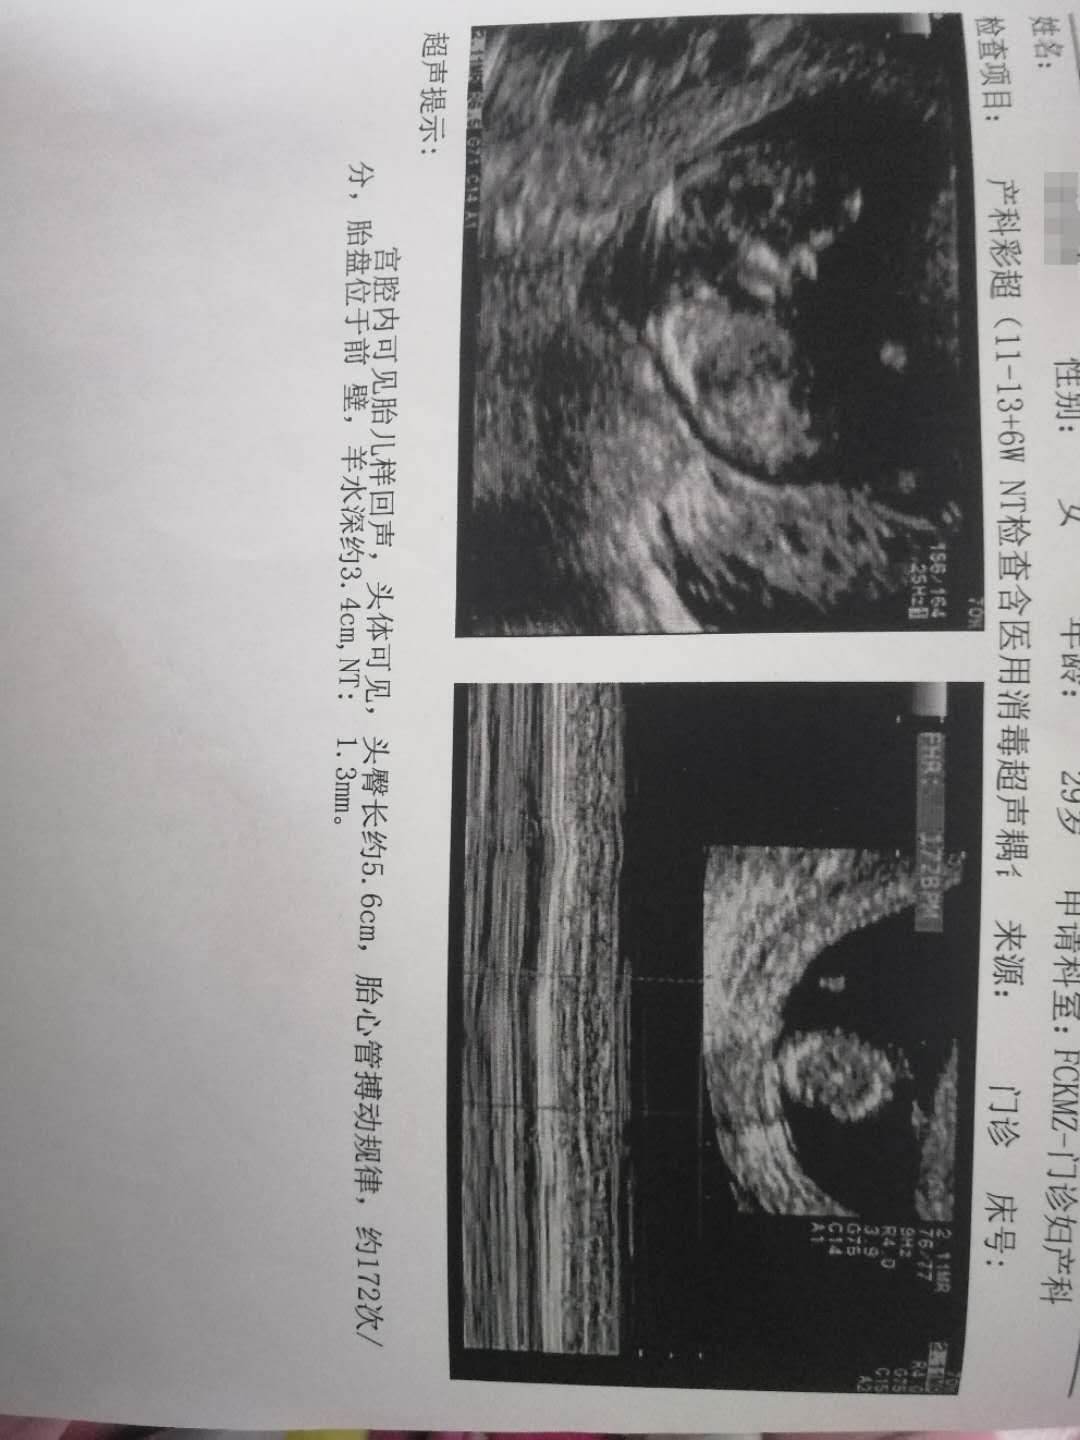

孕12周+5天

女宝